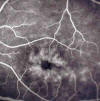

La prueba de imagen más importante en el diagnóstico de un EMC es la OCT. Se trata de una técnica no invasiva que determina la presencia de áreas quística rellenas de líquido en la región macular y permite la monitorización cuantitativa y cualitativa antes y después del tratamiento. La angiografía fluoresceínica (fig. 1) es una prueba de imagen alternativa; su ventaja respecto a la OCT es que los hallazgos asociados pueden ayudar a la etiología del EMC y su desventaja es que es invasiva y requiere de mayor tiempo (en ocasiones se requieren mas de 20 minutos para observar el acúmulo de líquido). Otras pruebas incluyen el electroretinograma, útil si existe la sospecha de una retinitis pigmentaria.

Fig. 1: Edema macular cistoide detectado en la angiografía fluoresceínica.